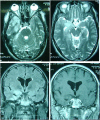

Figure 1

MRI axial T2 (A and B) and coronal fluid-attenuated inversion recovery image (C), showing a hippocampal lesion on hypersignal. Coronal T1 sequence with gadolinium injection (D) shows a small enhancement.